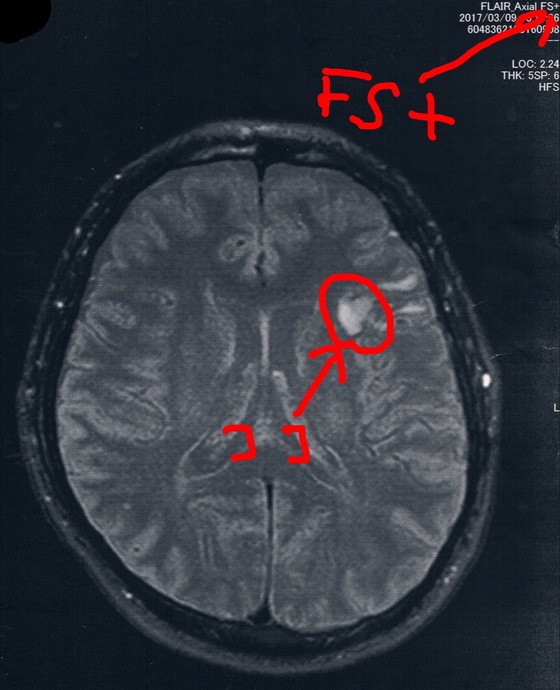

前回2017/3/9(手術後33ヶ月)のMRI画像